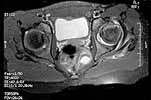

I appreciate some advise on this case. 11 y o girl doing high performance gymnastics in USA. On a fall over the left foot have done a forced medial rotation of the left hip, feeling pain on the buttock and thigh. Stopped the activity for a week and returning to sport, didn't reach the same performance, complaining of pain and limping when she make efforts, this lead her to abandon gymnastics. It have been diagnosed as Perthes disease. I am attaching xr and relevant mri. Your opinion is welcomed.

Regarding this case, I am grateful by your opinion. After careful analysis of the history and films, I am convinced that this is not a Perthes disease. In fact, on this case there are a violent traumatic event that have provoked the lesion, which is not compatible with Perthes. On the other hand, the MRI pattern is not what I am used to seeing. The patient presents a voluminous joint effusion and a image of anterior impaction of the femoral head with a thin layer of subchondral necrosis under the compacted zone (jb02).

In Perthes, the necrosed zone generally includes a deep thickness of the epiphysis. On the other hand, it doesn't seem to have articular cartilage thickening, one of the 1st signs of Perthes. Finally on the MRI one can see a rupture of the lateral rotator muscles, including gemelli, obturators and quadratus, with abundant extra-articular effusion, which never happens in Perthes disease and shows the violence of the accident (jb01).

As we interpret this patient's lesion, it is not Perthes nor traumatic AVN; it is a crush injury of the head with sub-chondral fracture and necrosis of the underlying bone tissue by impaction. The probable mechanism can be explained by the immature bone structure subjected to intense training. The young lady was doing an exercise that only a few athletes do - triple spinning, rotating the body anticlockwise and landing unbalanced over the left foot. Inertia violently medially rotated the limb, firstly stretching the lateral rotator muscles to its limit, then doing a impaction fracture of the anterior head on the anterior wall of the acetabulum, and finally, instead of a dislocation, muscular/tendinous rupture happens at the rotator muscles. We have proposed to complete the image study with a US scan and MRI on T1 sequence and sagittal plane. If we can confirm this type of lesion, we intend to do a transphyseal neck-head tunneling, dis-impaction of the head and bone graft thru the tunneling. The patient came this week from USA to be studied and treated on our hospital. I hope to be able to show you the new images next Monday.